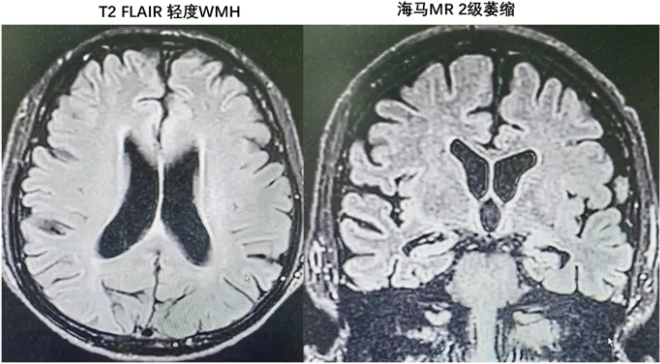

患者2:69岁女性,记忆力减退2年。MMSE=27;MoCA=24,认知域边界性正常,考虑主观认知下降(SCD)。外院颅脑MR提示白质损伤Fazekas 1 级;海马2级萎缩;Aβ PET检查视觉评估提示可疑阳性(外院检查,无原始图)。完善腰穿CSF AD生物标志物提示Aβ和ptau181可疑阳性,N(T-tau)阳性,但Aβ42/Aβ40比值正常。

患者3:70岁男性,记忆力减退4年余。受教育程度:大学。MMSE=27分,MoCA=17分,认知域提示记忆、语言、执行等多认知域受损,评估为MCI。颅脑MR提示白质损伤Fazekas 1级;海马2级萎缩;外院Aβ PET检查视觉评估(无原始图):双侧额叶皮层局部见放射性摄取增高。深圳湾实验室以小脑为参照验证后的全脑平均标准摄取值比= 1.08<1.11(阴性,但已接近界值)。Tau PET检查阴性。